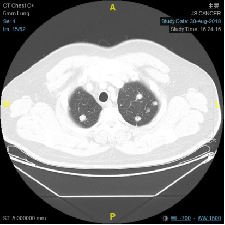

CT示:两肺多发转移瘤

2018-02-06: